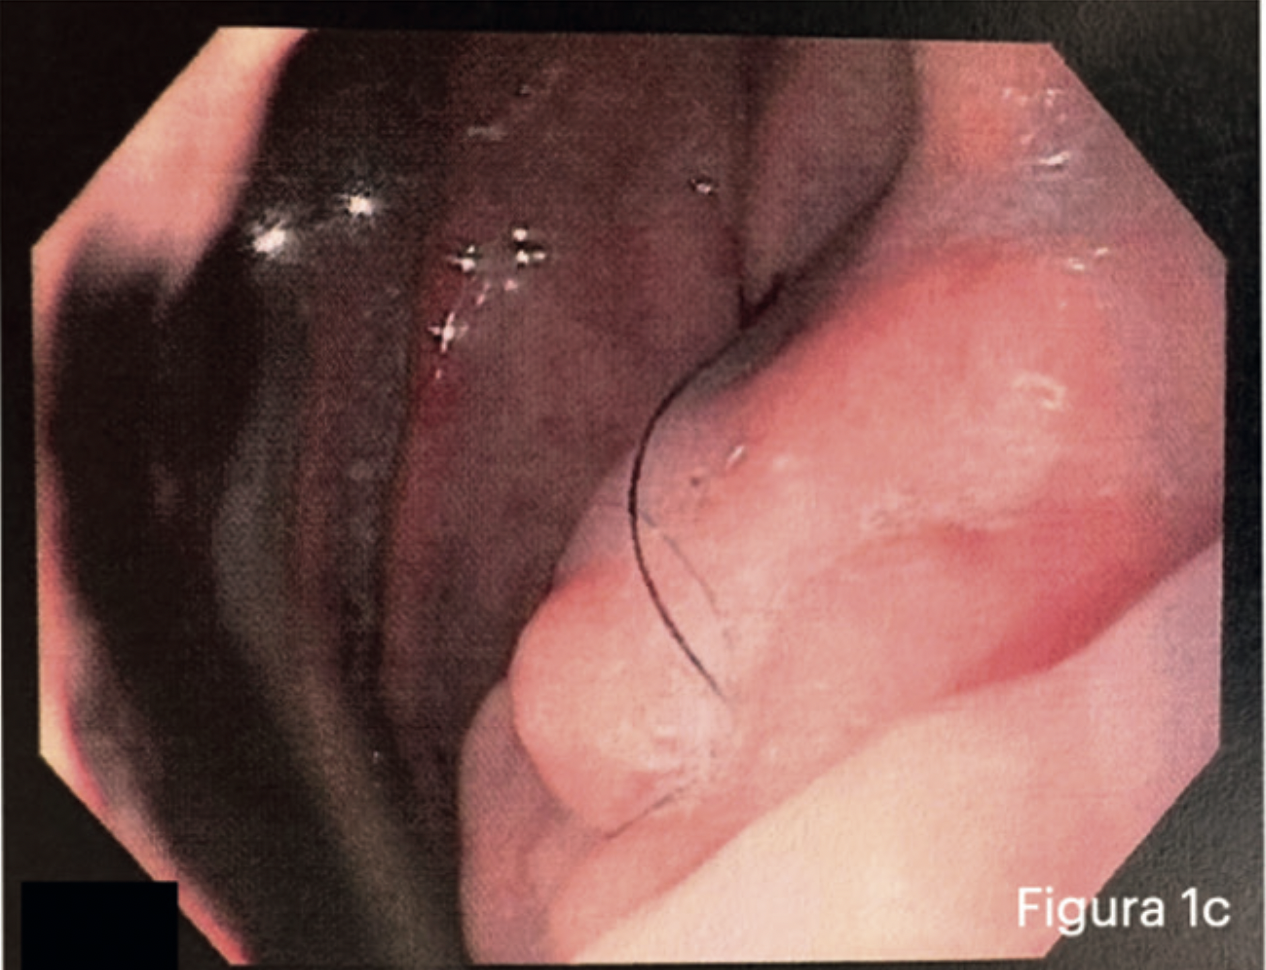

Resultados: Paciente masculino de 33 años que presenta cuadro de TVP (trombosis venosa profunda) que se decide complementar con Angiotc donde se constata aumento de volumen nodular en relación a la curvatura menor del estómago. Se complementa estudio con endoscopía digestiva alta que muestra lesión infiltrante, extensa en curvatura menor. Se decide realizar gastrectomía total laparoscópica. Estudio histopatológico muestra en curvatura menor, histopatología compatible con teratoma maduro. Paciente con evolución satisfactoria post operatoria se decide alta médica, control a los 7 meses post operado sin complicaciones.